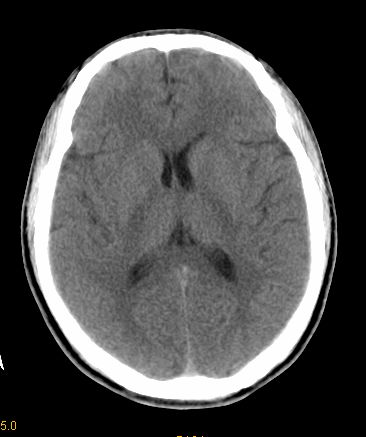

男 42岁 头痛20天

左顶叶见片状低密度影,边界不清,内见斑片状等密度影。考虑转移性肿瘤可能性大,建议ct增强或mr增强扫描。建议胸部检查,排除肺部病变。

左顶叶见片状低密度影,内似见结节状略高密度影,建议增强扫描。

左侧顶叶低密度灶,性质待定;建议行ct增强扫描或mri检查。

左顶叶见片状低密度影,边界不清,内见斑片状等密度影。考虑转移性肿瘤可能性大,建议ct增强或mr增强扫描。建议胸部检查,排除肺部周围型腺癌。